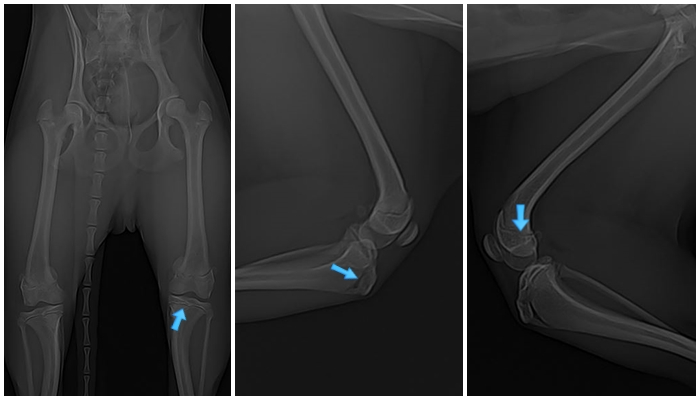

정확한 진단을 위해 신체검사와 방사선 촬영을 진행하였습니다.

수술 전 방사선 검사 사진 / 출처: 라온동물메디컬센터

검사 결과, 양측 슬개골 탈구 2기 후반~3기 초반으로 확인되었습니다.

이 시기에는 슬개골이 자주 탈구되며, 관절 연골의 마모가 시작될 수 있어 적극적인 치료가 권장되는 단계입니다.

방사선 검사상 C는 아직 성장판이 닫히지 않아 골격 성장이 진행 중인 어린 환자라는 점도 함께 확인되었습니다.